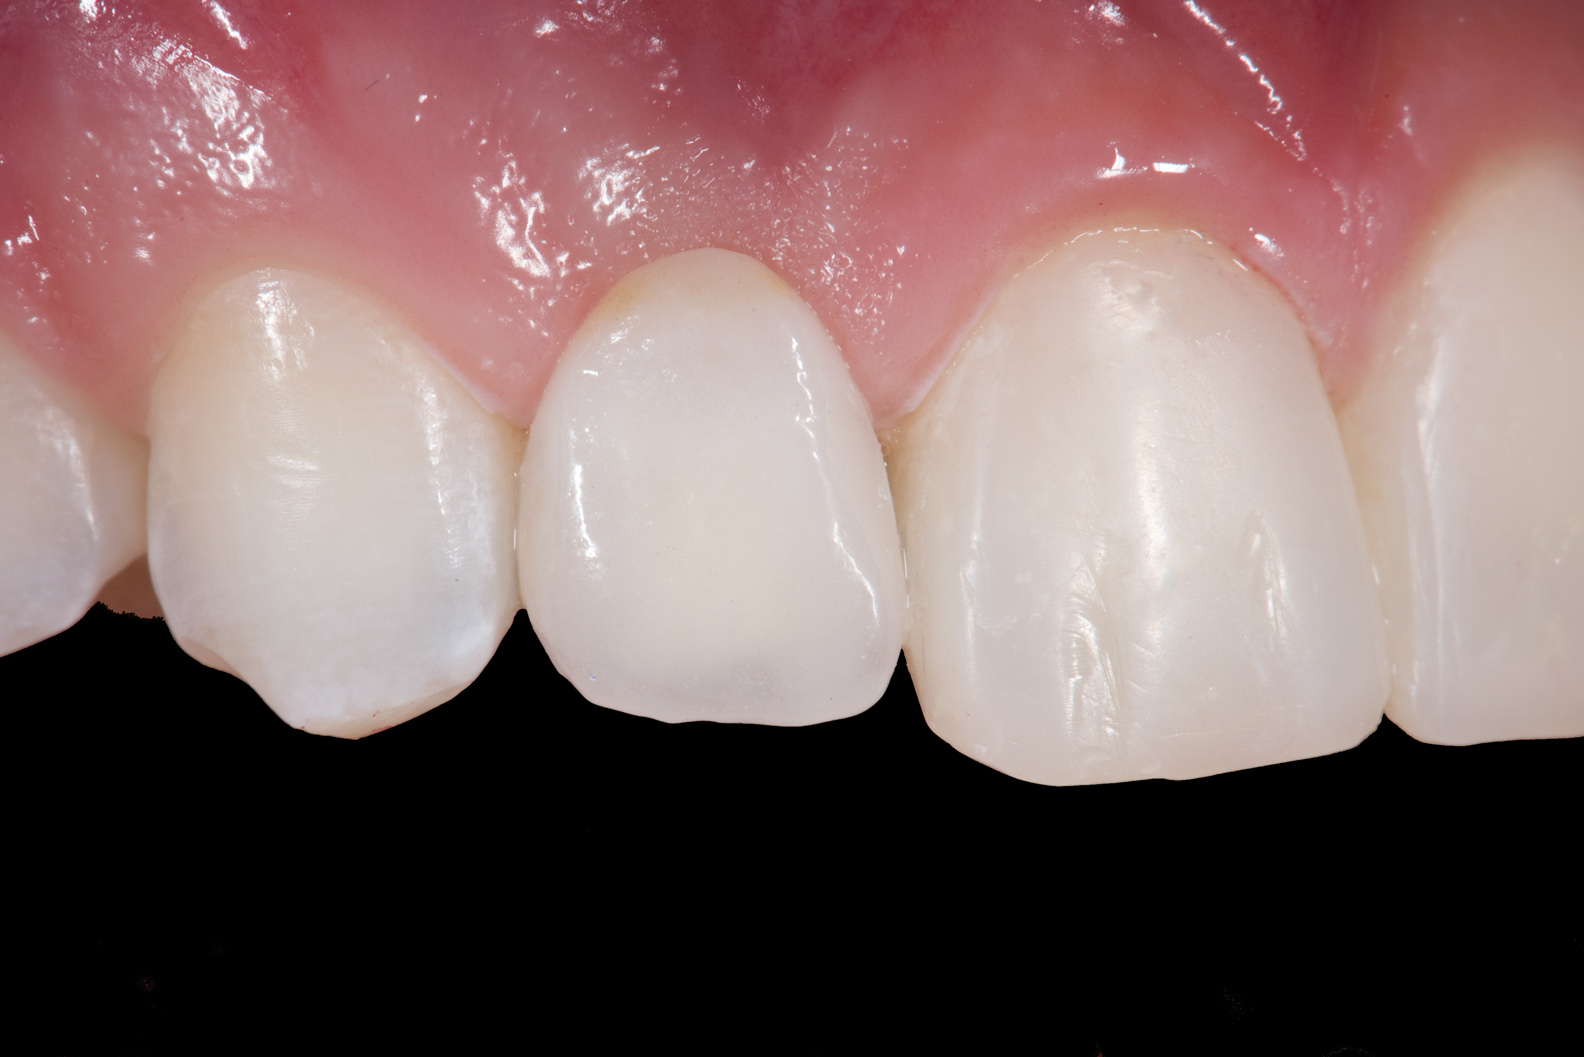

Fig 3. After resin-based composite bonding of the three incisors.

Figure 3